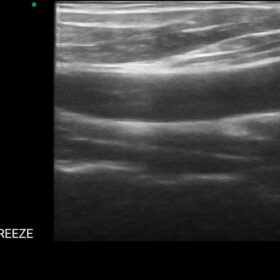

Dormed WiFi Probe Image Gallery and Videos

Linear Array WiFi Probe for Vascular and Small Parts